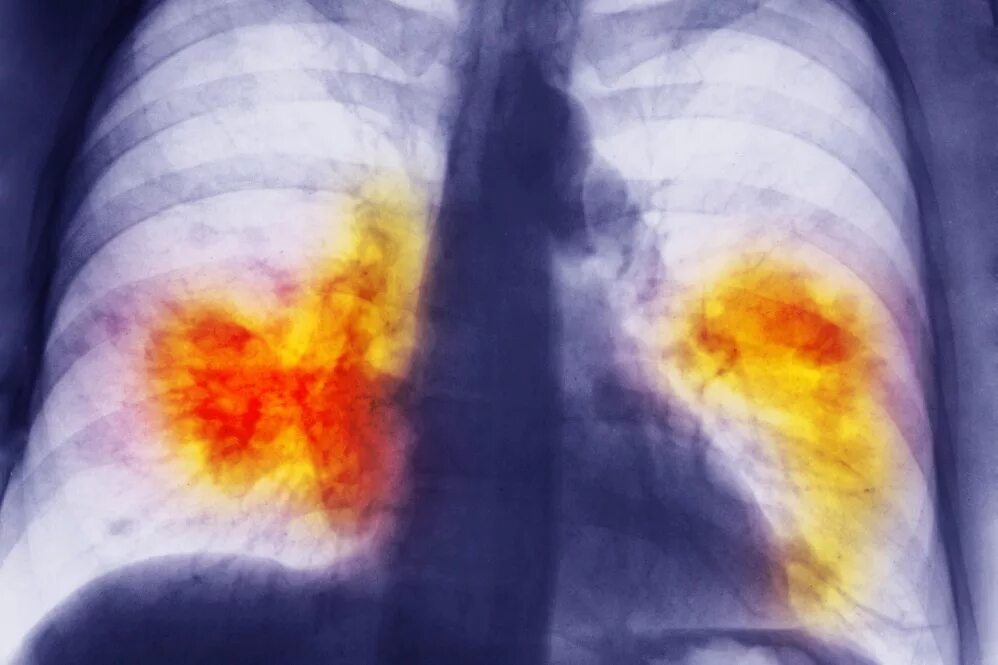

Помощь при туберкулезе легких